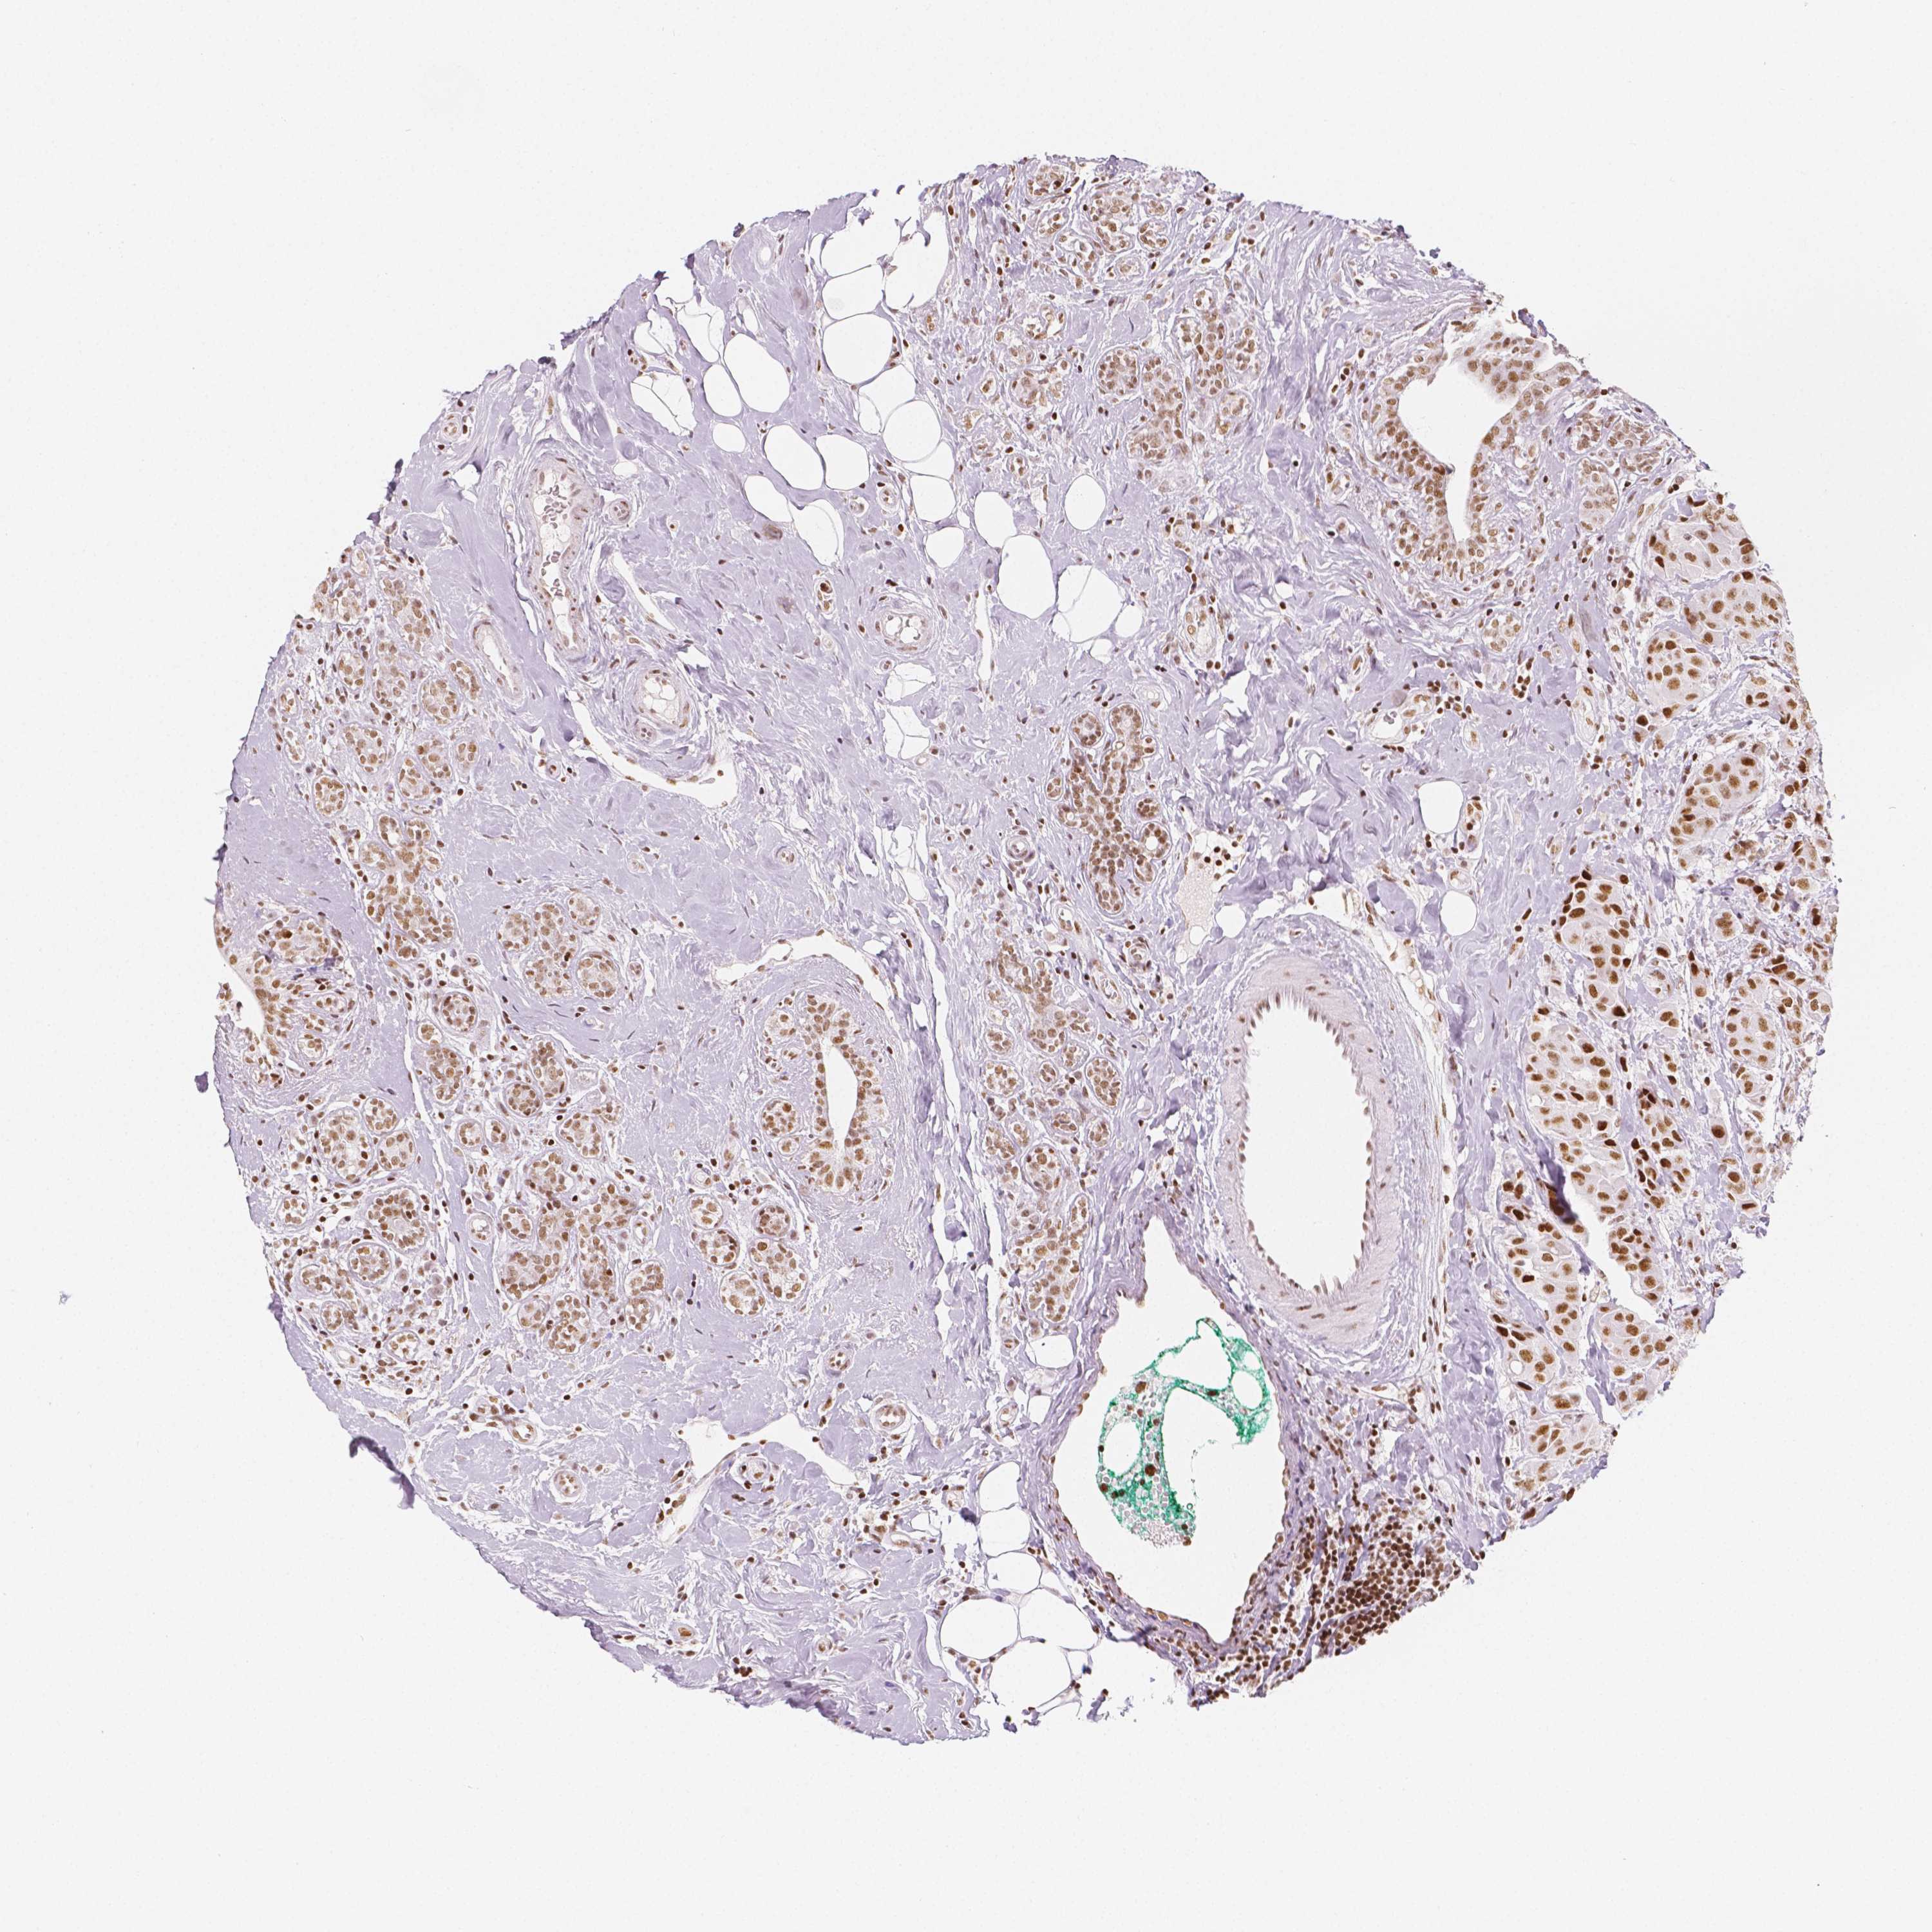

BRCA TCGA BRCA VALIDATION PROTEIN EXPRESSION

ANTIBODIES

AND

VALIDATION